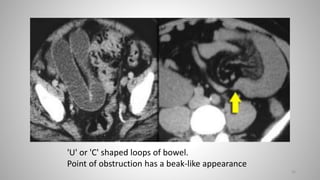

'U' or 'C' shaped loops of bowel.

Point of obstruction has a beak-like appearance

Closed loop obstruction with radial array of dilated loops.

There is bowel wall thickening and mesenteric edema indicating ischemia